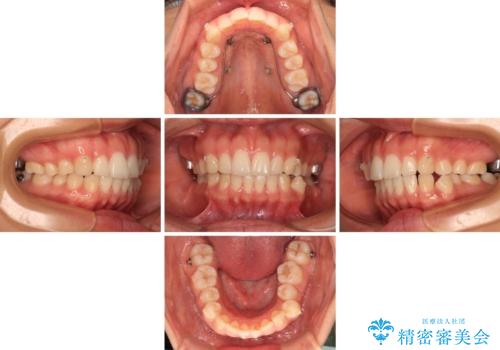

【モニター】突出した前歯 補助装置を併用したインビザライン矯正

- 上下前歯が非接触となり、前方に突出していることを気にして来院された患者様です。

咬合力が強く、全体的に歯がすり減っているため、インビザライン単独での上顎歯列移動は困難と判断し、補助装置により上顎歯列を後方移動させ、その後インビザラインにて仕上げていくこととしました。

補助装置なしでも改善できる可能性はありましたが、補助装置で確実性を上げ、短期間できっちりと仕上げることができました。